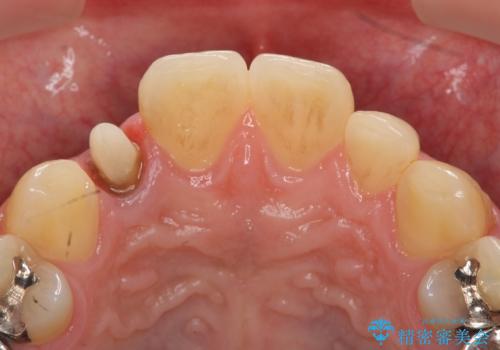

- 金属を使っていない被せ物に替えたいといらっしゃった方の症例です。

再根管治療終了後、オールセラミッククラウンによる補綴を行いました。